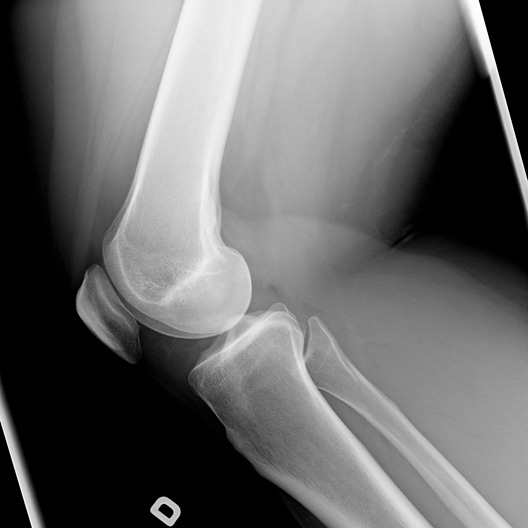

• radiografia della rotula: si tratta di un esame utile per osservare lo strato cartilagineo;

• risonanza magnetica: questa tecnica permette di rilevare con maggior precisione eventuali danni alla cartilagine e fornisce informazioni sulla stabilità articolare e su eventuali altri tessuti molli danneggiati;

• artroscopia diagnostica: questa tecnica consente allo specialista di osservare direttamente la cartilagine, i tendini e altre strutture articolari. L’artroscopia è una procedura tanto diagnostica quanto operativa.